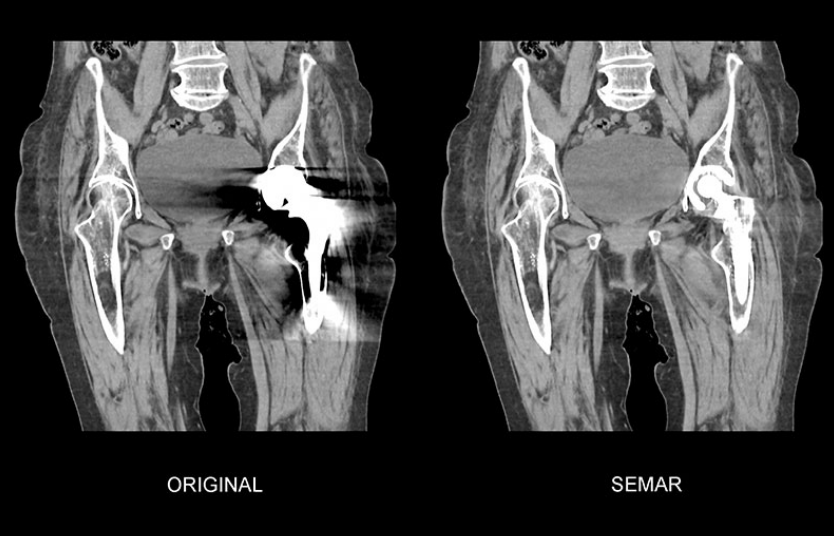

また、画像のノイズや放射線被ばくを低減するAiCEという機能や⾦属による画像の影響を軽減するSEMARという機能が備わっております。そのため、⼿術などで体内に⾦属を留置していてもCT画像への影響が少なくなりました。

股関節に金属が留置されています。ORIGINAL画像では、金属の周りが黒く抜けてしまっており、診断がしにくいです。SEMAR画像では、黒く抜けている部分が改善されています。